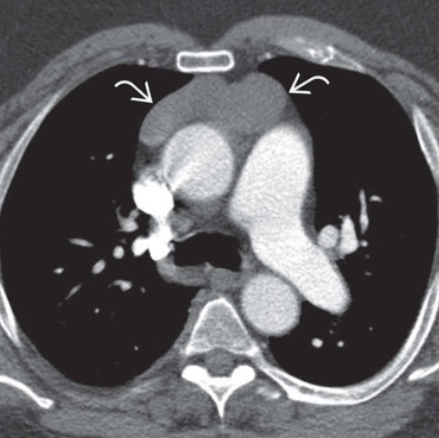

Phình động mạch chủ ngực (Thoracic aortic aneurysm)